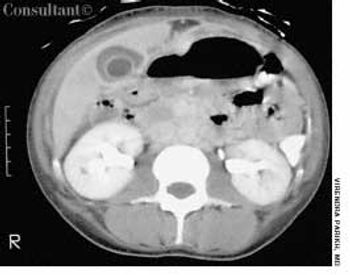

An obese 52-year-old woman with a 5-year history of type II diabetes mellitus had odynophagia and dysphagia for several days. She described the sensation as food “sticking” in her chest. She also complained of vaginal itching, polyuria, and polydipsia. The only remarkable finding on physical examination was candidal vaginitis. The patient did not smoke cigarettes or drink alcoholic beverages, and there was no history of recent weight loss.